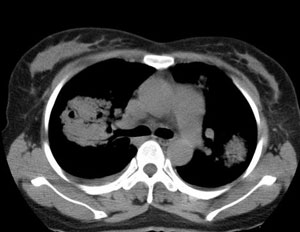

女性,30岁。

病史为胸痛20多天,无畏寒发热,无消瘦,无咳嗽咳痰。总之症状很逍遥。

临床以胸痛待查收住入院。

双肺野可见散在大小不等结节及肿块影,内密度不均匀,边缘部分清,部分欠清,纵隔未见明显肿大淋巴结.右侧胸腔少理积液.结合临床,考虑韦格肉芽肿可能吧,巨淋巴增生,结节病,特殊感染都要考虑.转移瘤临床不象.

多发、内可见含气支气管征,边界不清;纵隔内未内见明显肿大淋巴结。右侧少量胸腔积液。

两肺散在分布大小不等的肿块及结节影,边缘毛糙,有分叶、毛刺,病灶密度不均匀,可见支气管充气相与空泡征。病变大多位于胸膜下,可见胸膜凹陷及胸腔积液。气管腔静脉间可见小结节影。

病人临床仅为胸痛,暂不考虑感染性病变。

考虑多发结节型细支气管肺泡癌。

考虑肺真霉菌病;心脏增大,肺动脉增宽